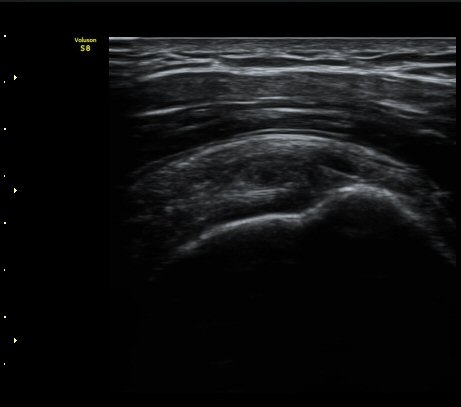

°ß°©ÇÏ±Ù°Ç Á¾´Ü¸é°Ë»ç¿¡¼­ ƯÀÌ ¼Ò°ß ¾øÀ½

(no specific abnormal findngs with longitudinal scan of subscapularis tendon) »çÁø 3